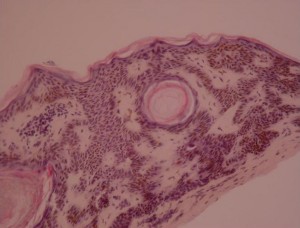

E. Irritated (activated)

{Wade, 1979} The epidermis contains epidermal nests called squamous eddies{Pierson, 2003}. The cells are intensely eosinophilic and are disposed in an onion peel fashion {Kao, 2000}. Indeed, this reaction would represent an immunological reaction{Berman, 1980; Berman, 1982} against SK lesions which leads the basaloid cells to convert into squamous-like cells. Squamous eddies, as well as the basal part of SKs, contain apoptotic cells Pesce, 2000}.The keratinocytes in the squamous eddies (or elsewhere?) are increased in size {Pesce, 2000}. Discrete to moderate atypia and mitotic cells, in contrast with other types may be present.

F. Inverted follicular keratosis (follicular poroma, basosquamous cell acanthoma)

This belongs to the irritated SK subtype. It shows contrary to “classical” irritated SK an endophytic pattern of growth.

{Pierson, 2003}Histologically it resembles irritated SK. Squamous eddies are present, but they sometimes keratinize in their center. What is different, is that there is a bulb like endophytic proliferation of eosinophilic keratinocytes, which have a basaloid or squamous-like morphology. The lesion is bordered by basaloid cells arranged in a palissade manner.